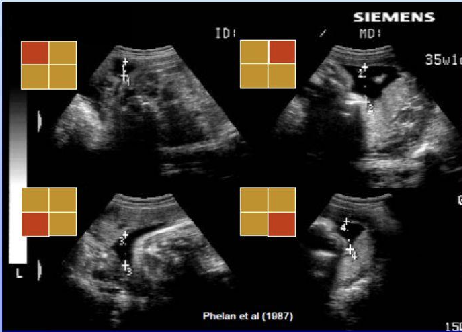

¿Cómo se evalúa el volumen de LA?

Índice de Phelan (suma 4 cuadrantes): Valor Normal: 8-16 cm. 📏

¿Qué valor de ILA indica oligoamnios?

<8 cm. ⚠️ VN: 8 a 16cm ## Footnote * Oligoamnios representa sin duda mayor riesgo para el feto * ILA menor de 8 indica Oligoamnios

10. ¿Qué valor de ILA indica oligoamnios? A. >16 cm B. 8-16 cm C. <8 cm D. >5 cm

C. <8 cm ILA: Índice de Líquido Amniótico. ⚠️